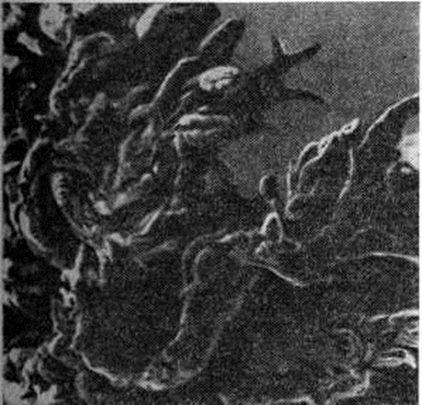

Рис. 1.

Электронограмма синовиальной оболочки сустава при ревматоидном артрите, полученная с помощью сканирующего микроскопа: видны ворсинчатые разрастания; ×35 000.

В суставах при развёрнутой клинические, картине заболевания обнаруживается ворсинчатое разрастание синовиальной оболочки (рисунок 1), в части случаев наползающей в виде паннуса на поверхность суставного хряща. При этом в суставном хряще определяются эрозии, трещины, щели; его остатки сухие и зернистые на вид. В суставных полостях обнаруживается увеличенное количество вязкой мутной синовиальной жидкости, постоянно отмечается утолщение и склероз суставной капсулы, имеются фиброзные спайки. Полная облитерация суставной полости спайками ведёт к развитию фиброзного анкилоза (смотри полный свод знаний). Пролиферация остеоидной ткани сопровождается развитием остеофитов (смотри полный свод знаний) и костных анкилозов.